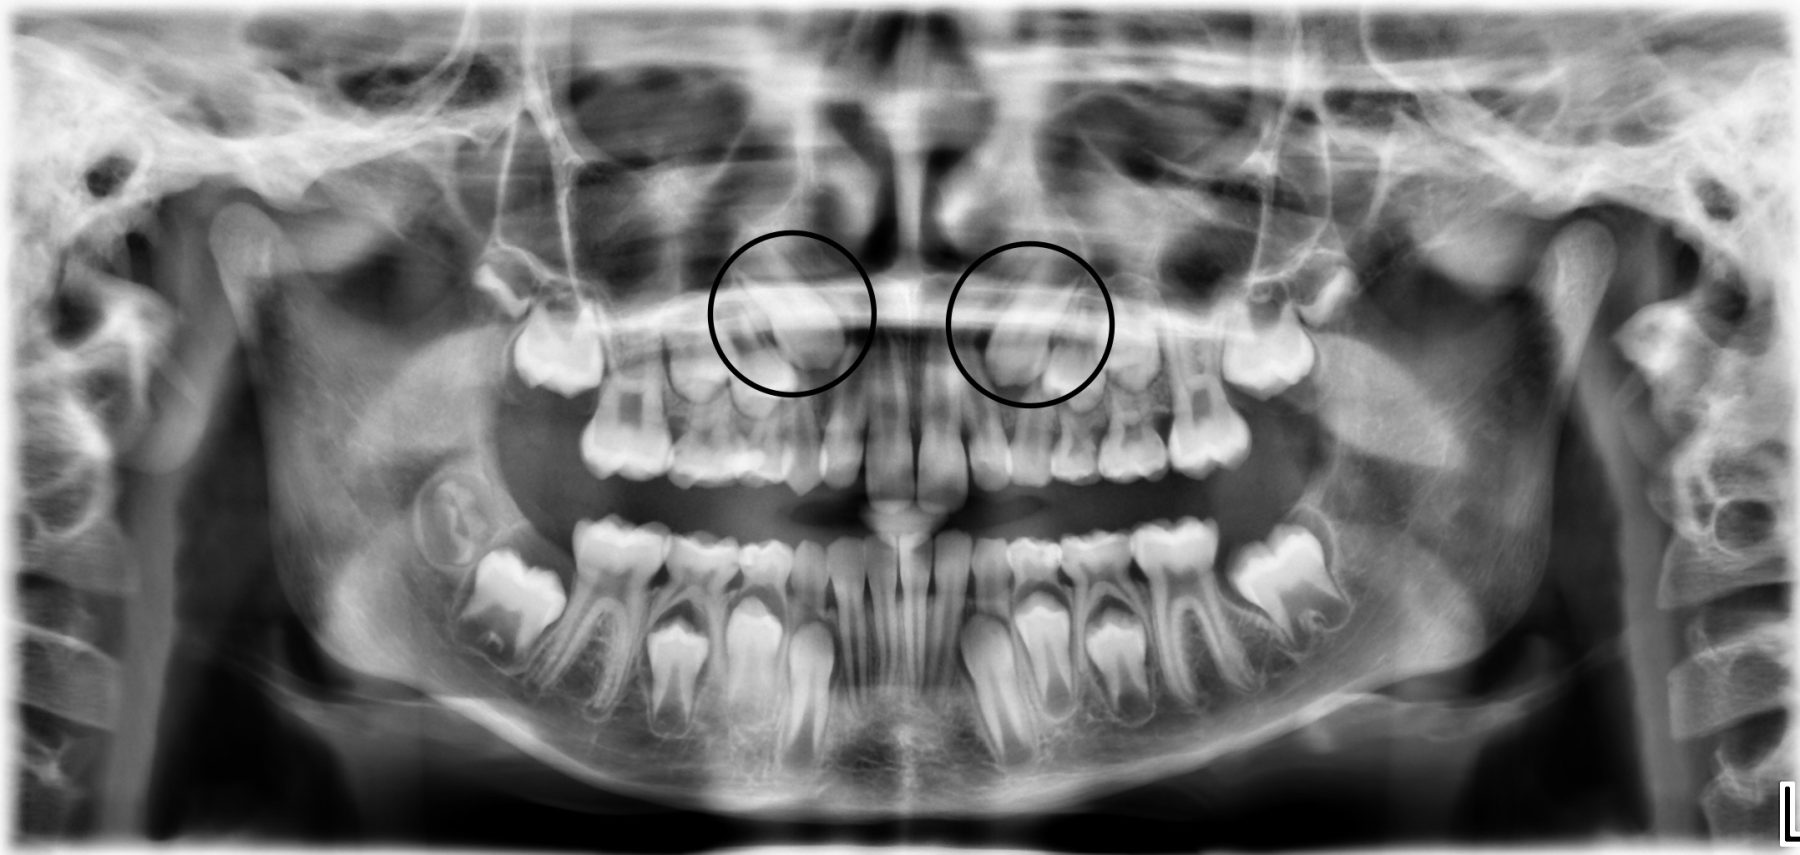

De röntgenfoto toont dat de blijvende hoektanden, die nu nog vrijwel naast de neusbodem in de kaak liggen, weinig ruimte zullen hebben om door te breken.